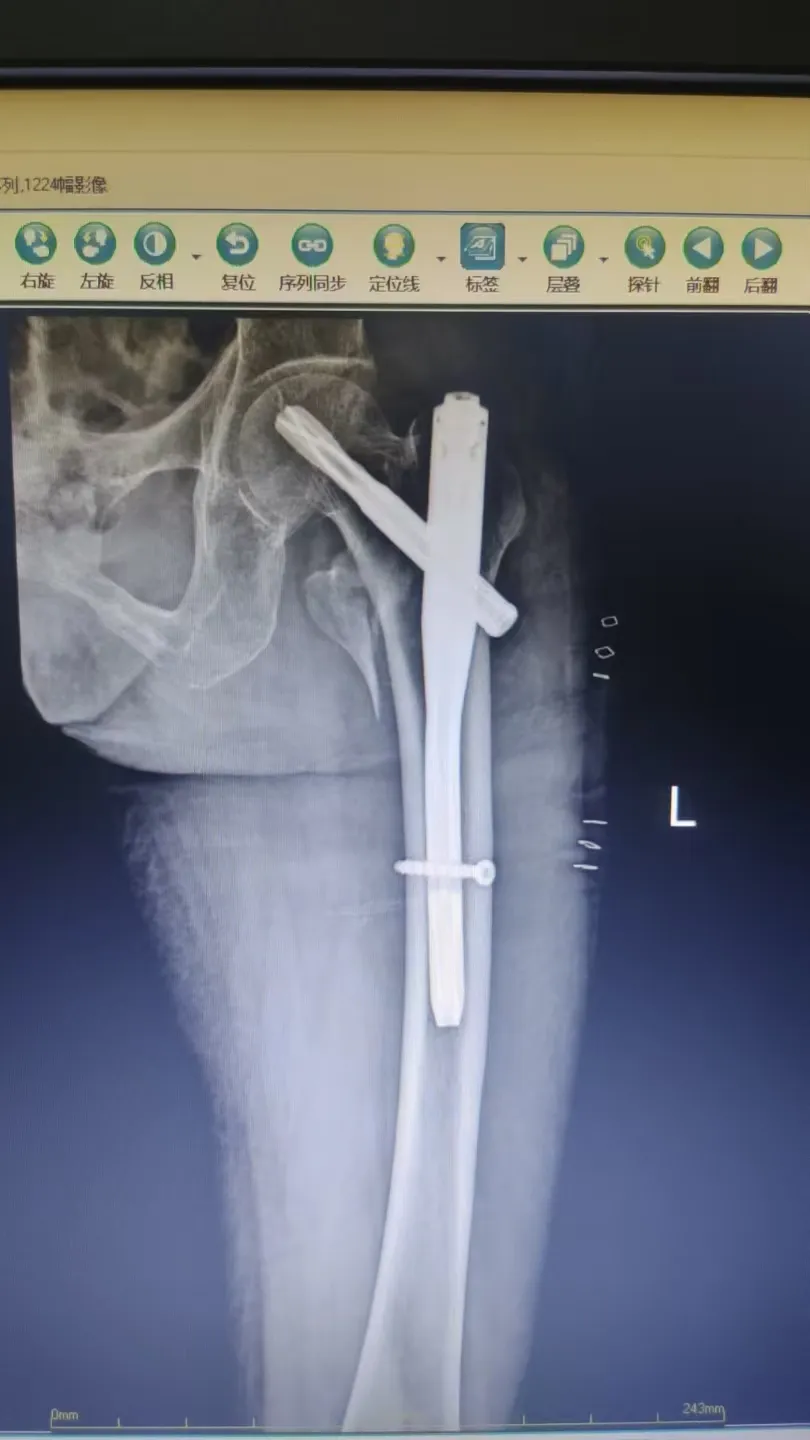

PFNA術(shù)式屬于髓內(nèi)固定系統(tǒng),具有創(chuàng)傷小、固定牢、出血少、愈合快的優(yōu)點(diǎn),尤其適用于高齡轉(zhuǎn)子間骨折患者,是提升手術(shù)安全性與效果的關(guān)鍵技術(shù)。

手術(shù)在麻醉科的保駕護(hù)航下順利完成。術(shù)中采用微創(chuàng)小切口,精準(zhǔn)置入PFNA髓內(nèi)釘。

術(shù)后復(fù)查顯示骨折對(duì)位對(duì)線良好,患者疼痛顯著緩解,在醫(yī)護(hù)人員指導(dǎo)下逐步開始康復(fù)鍛煉,重燃站立行走的希望。